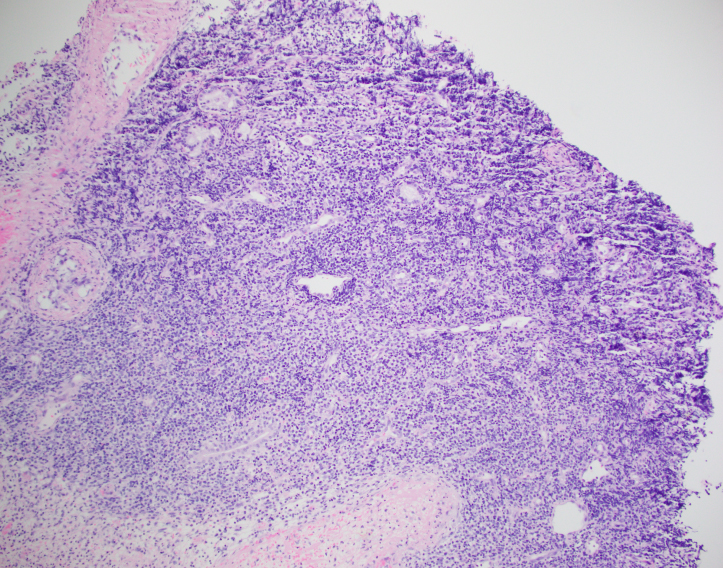

A 23 year old man presented to the hospital with recurrent fever up to 103F with associated nausea and vomiting, epistaxis, watery diarrhea, dyspnea, and decreased appetite for several days. Blood cultures from admission were positive for MSSA and a stool PCR was positive for Vibrio species. He was admitted and treated for sepsis. His CBC demonstrated a marked pancytopenia ( WBC count 0.6 K/μL) and the hematopathology team was consulted to review the peripheral blood film.

Review of the peripheral blood confirmed a markedly pancytopenic picture with virtually no leukocytes in the region of best RBC “spread” (Image 1A). In the periphery of the smear (1B and C) clusters of leukocytes were noted where left-shifted granulocytes were seen. Many demonstrated nuclear irregularity and abnormal granulation (B) and some showed the presence of numerous Auer rods (Image 1C, arrows).

The presence of abnormally granulated immature neutrophilic precursors, and cells with numerous Auer rods was morphologically compatible with acute promyelocytic leukemia (APL) and a rush preliminary diagnosis was rendered. The patient was started on ATRA therapy and FISH for PML-RARA was expedited.

Acute promyelocyticleukemia (APL) is characterized as an acute myeloid leukemia in which promyelocytes with the PML-RARA fusion predominate. The PML-RARA fusion is the result of a balanced translocation between chromosomes 15 and 17, designated ast (15;17)(q24.1;q21.2). The promyelocyte progenitor cell is the cell of origin of APL. APL occurs most frequently in middle aged individuals, but can occur at any age.